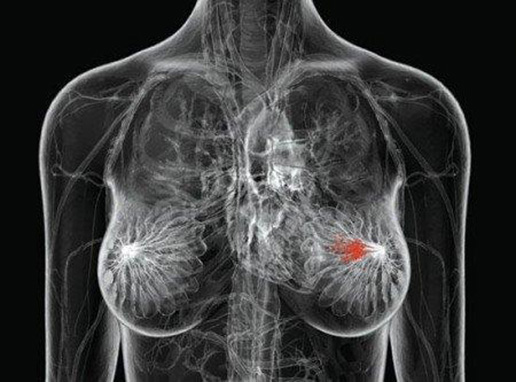

Wprowadzenie W województwie wielkopolskim obserwuje się trend wzrostu nowych zachorowań z roku na rok. W 2000 roku liczba nowych zachorowań wynosiła 1192, w 2003 roku – 1197, 2004 roku – 1200 osób, a już w 2012 roku wykryto 1600 przypadków nowotworów piersi. Zasadnym zatem wydaje się podjęcie badań mających na celu ocenę wiedzy personelu medycznego oraz pacjentek z tego obszaru. Praca jest…